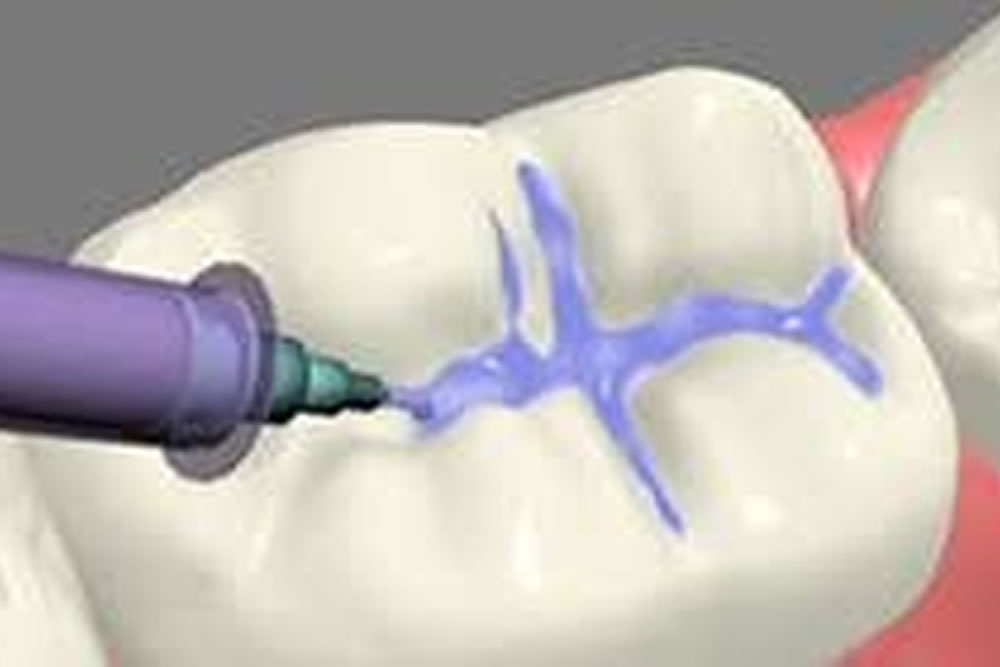

④CRを充填する

虫歯で失われた歯を補うようにCRを充填していきます。大きさ、部分はその虫歯によって異なるため同じ充填はありません。それぞれの歯に合わせて流れのいいもの、ペースト状のもの、色を合わせて修復していきますので、オーダーメイドの治療と言えるかもしれません。